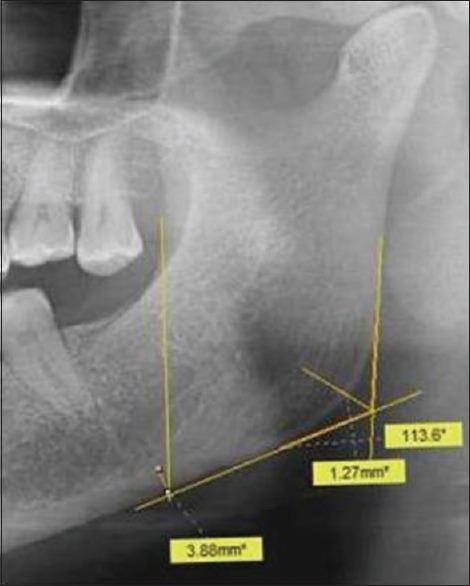

Osteoporosis is a specific condition which is characterized by low bone mineral density (BMD) and deterioration of bone structure resulting in an increased susceptibility to fractures. It contributes to a great deal of morbidity and mortality, and is a large burden to the healthcare system, especially in the case of the elderly population. In the last four decades, a plethora of studies have reported characteristic oral radiographic findings in the early stages of osteoporosis, suggesting the possible use of oral radiographic signs for the early detection of the condition. Digital orthopantomographs (OPGs) are usually taken for the screening of dental patients during routine dental evaluations. These radiographs and the characteristic changes seen on them may have a significant role in the screening for initial osteoporotic changes. A number of precise radiomorphometric indices of the mandible have also been developed to allow quantification of the mandibular bone mass for identification of the initial signs of osteoporosis. The present review focuses on the possible role of panoramic radiographs in the initial screening for osteoporosis in dental clinics in high-risk groups.

骨质疏松症是一种特殊的病症,其特征是骨矿物质密度(BMD)低且骨结构恶化,导致骨折易感性增加。它导致大量的发病和死亡,给医疗保健系统带来巨大负担,尤其是在老年人群中。在过去的四十年里,大量研究报告了骨质疏松症早期阶段典型的口腔放射学表现,这表明口腔放射学征象可能用于该病症的早期检测。在常规牙科评估期间,通常会拍摄数字化曲面断层片(OPG)以筛查牙科患者。这些X光片及其上所见的特征性变化可能在初步骨质疏松症变化的筛查中发挥重要作用。还开发了一些精确的下颌骨放射形态计量学指标,以便对下颌骨质量进行量化,从而识别骨质疏松症的初始迹象。本综述重点关注全景X光片在高危人群牙科诊所骨质疏松症初步筛查中的可能作用。